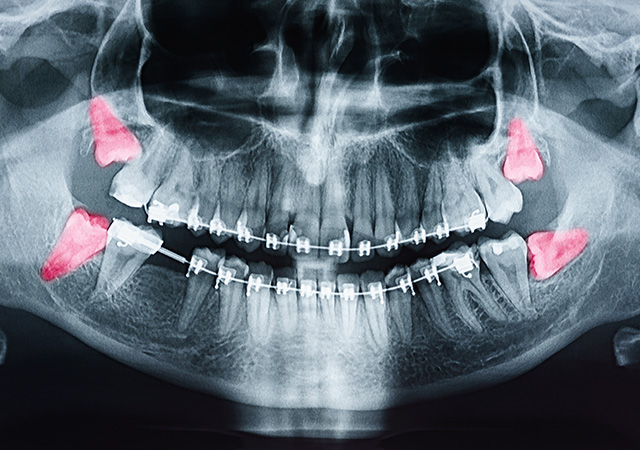

多くの方が、17歳~30歳頃に親知らずが生えてきます。(現代の若年層の方は、硬い物よりも柔らかい物を好んで食べる傾向にあるため、親知らずが生えてこないケースも多いです。)親知らずとは、お口の中の一番奥の歯(前歯から数えて8番目の歯)のことをいいます。

永久歯の中で、一番最後に生えてくるためスペースが無く、横や斜めに向いていたり、骨の中に埋まったまま生えてこない場合もあります。

このような親知らずを放っておくと歯茎がとても腫れてしまったり、手前の7番目の歯をむし歯にしてしまうことも多く、トラブルの原因になりがちです。抜歯をすることに抵抗がある方も多いかと思いますが、大きな問題になる前に抜歯(その文字の通りになりますが、歯を抜くことです。)した方が良い場合もあります。学校やお仕事、子育てなどが落ち着くタイミングでどうぞご相談ください。抜歯が難しくない場合は複数本を同日に抜歯することも可能です。